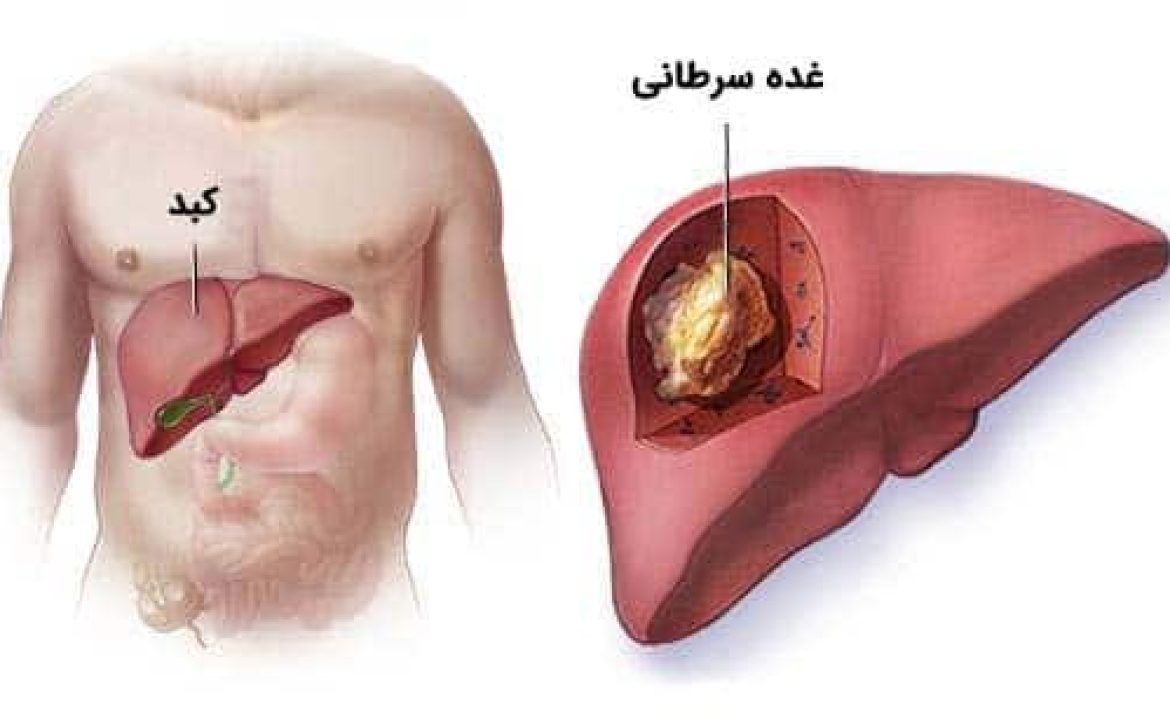

همانطور که گفته شد، عفونت هلیکوباکتر یکی از عوامل شایع زخم معده است. برخی از گونههای این باکتری میتوانند خطر ابتلا به سرطان معده را افزایش دهند؛ بنابراین درمان زخم معده باید با جدیت دنبال شود.

همچنین به یاد داشته باشید که درمان نکردن زخم معده میتواند به تدریج باعث آسیب جدی به بافت معده و حتی افزایش خطر ابتلا به سرطان شود؛ بنابراین در صورت داشتن مشکلات گوارشی، حتماً موضوع را با پزشک مطرح کنید.